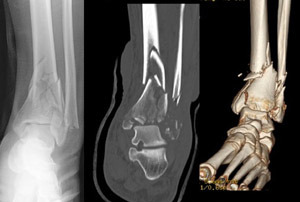

22. 경골 천정 골절이란 무엇인가?

경골 천정 골절은 거골의 밀착으로 인해 원위 경골의 관절내 골절을 말하는데, 종종 분쇄 형태로 나타난다.

△ Tibial plafond fracture (이미지 출처 : http://orthoinfo.aaos.org/topic.cfm?topic=A00527)